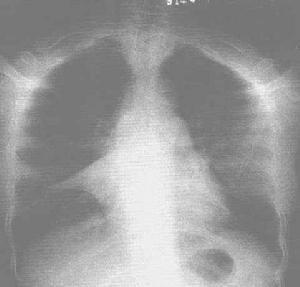

农民肺(farmer’s lung,FL)是因吸入含有嗜热放线菌的有机粉尘而引起的一种外源性变应性(过敏性)肺泡炎[extrinsic allergic(hypersensitivity)alveolitis]。患者多从事农业生产,故称“农民肺”。此外,还有甘蔗尘肺、蘑菇尘肺、土豆尘肺、湿化器肺(或“空调机肺”)等,均可因其生活环境含有大量嗜热放线菌而发生本病。有人将过敏性肺炎(hypersensitivity pneumonitis)归入此类疾病,但过敏性肺炎含义更广泛,应加以区别。国外有关农民肺的报道始于1932年,但当时对其病因不明,至1962年Pepys等在农民肺患者血清中发现了抗嗜热放线菌抗原的抗体后,才确认本病是与Ⅲ型变态反应有关的疾病。我国在1981年始有经尸检证实的农民肺病例报道。